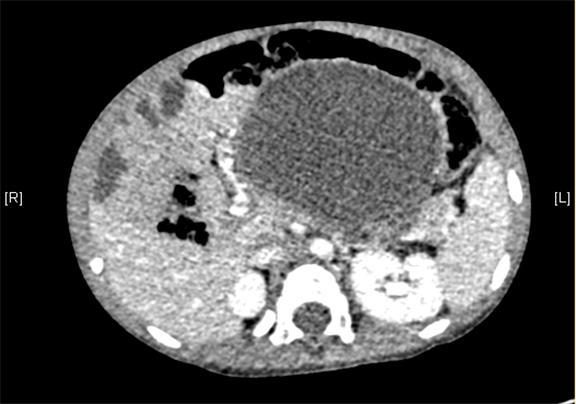

腹部三维动态CT:腹腔巨大囊性占位性病变,考虑肠系膜来源良性病变可能性大,腹腔肠系膜淋巴管瘤?

术前CT检查:

动脉期